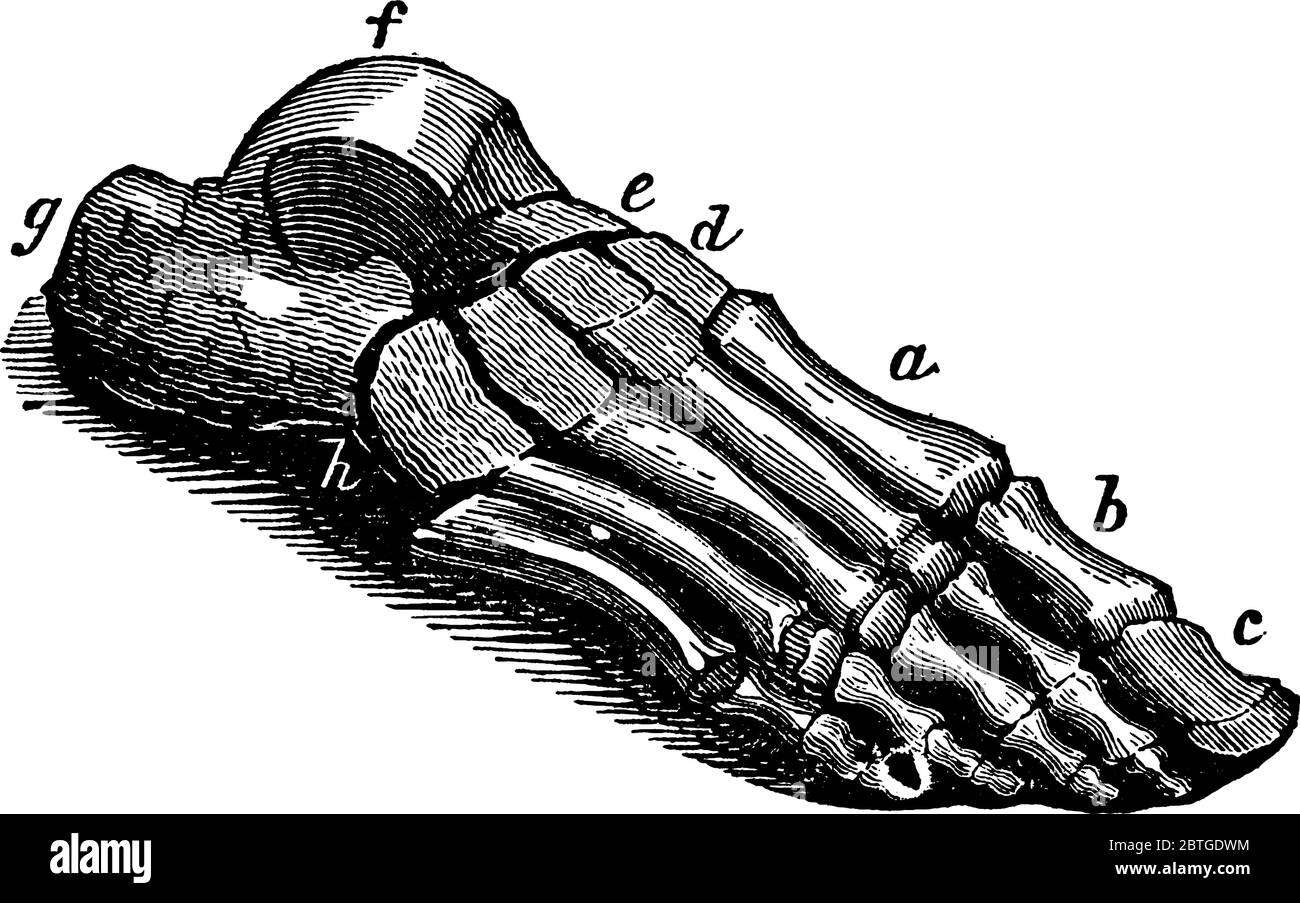

RF2BTGWJJ–Schéma d'un pied humain, l'un est la vue de côté et l'autre a de la semelle, dessin de ligne vintage ou illustration de gravure.

RF2BTGDWM–Les os de la Tarsal du pied sont situés dans le milieu du pied et les zones de l'arrière du pied humain, dessin de ligne vintage ou illustration de gravure.

RF2B74PR1–Le pied est construit sous la forme d'une demi-dôme ou d'une demi-voûte, d'un dessin vintage ou d'une gravure.